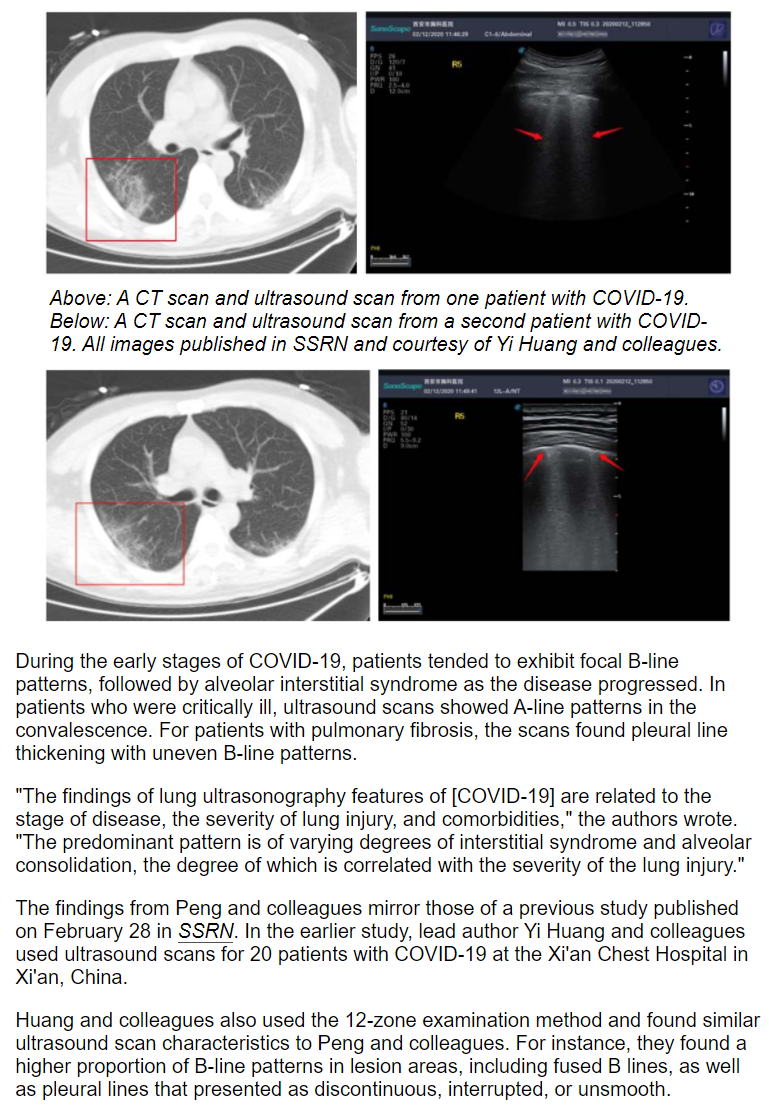

日前,一篇题为Ultrasound can be used for patients with COVID-19的报道在美国著名影像学论坛AuntMinnie.com发表。特约撰稿人Theresa Pablos在文章中写到:2020年2月28日,西安市胸科医院黄毅团队《A Preliminary Study onthe Ultrasonic Manifestations of Peripulmonary Lesions of Non-Critical Novel Coronavirus Pneumonia (COVID-19)》的预印本论文上线SSRN网站平台,在全球范围内率先公布了新型冠状病毒肺炎肺周病变超声表现。

这项研究为2020年1-2月份在西安市胸科医院收治经临床确诊的非重症期新型冠状病毒肺炎(COVID-19)患者共20例,均行常规二维超声及彩色多普勒超声检查,观察病灶在超声影像学下的图像特征。